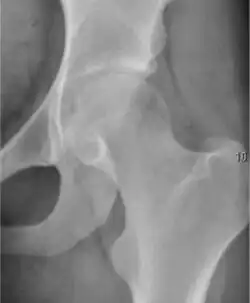

Projectional radiography ("X-ray") is the first imaging technique of choice in hip pain, not only in older people with suspected osteoarthritis but also in young people without any such suspicion. In this case plain radiography allows categorization as normal hip or dysplastic hip, or with impingement signs, pincer, cam, or a combination of both.[1]

X-Ray

Projectional radiography ("X-ray") is currently useful not only in older people in whom osteoarthritis of the hip is suspected but also in younger people without osteoarthritis, who are being evaluated for femoroacetabular impingement (FAI) or hip dysplasia.[1]

Plain radiography allows us to categorize the hip as normal or dysplastic or with impingement signs (pincer, cam, or a combination of both). Besides these, pathologic processes like osteoarthritis, inflammatory diseases, infection, or tumors can also be identified (Figure 1).[1]

Figure 1.

-

Radiography in normal hip -

X-ray in pincer impingement type of hip dysplasia -

X-ray of cam -

Hip in osteoarthritis -

Septic arthritis

X-ray in pediatrics